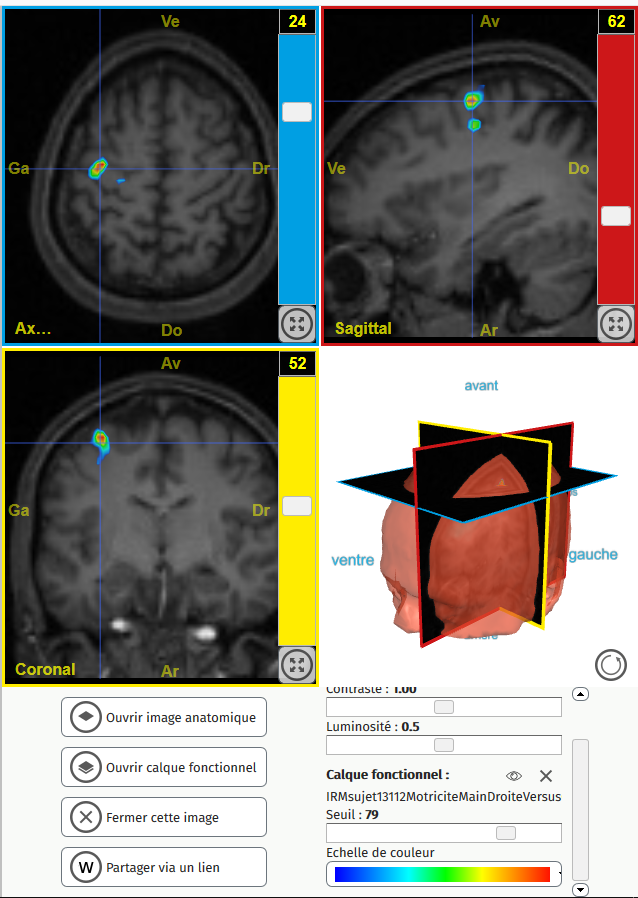

13112MotriciteMainDroite